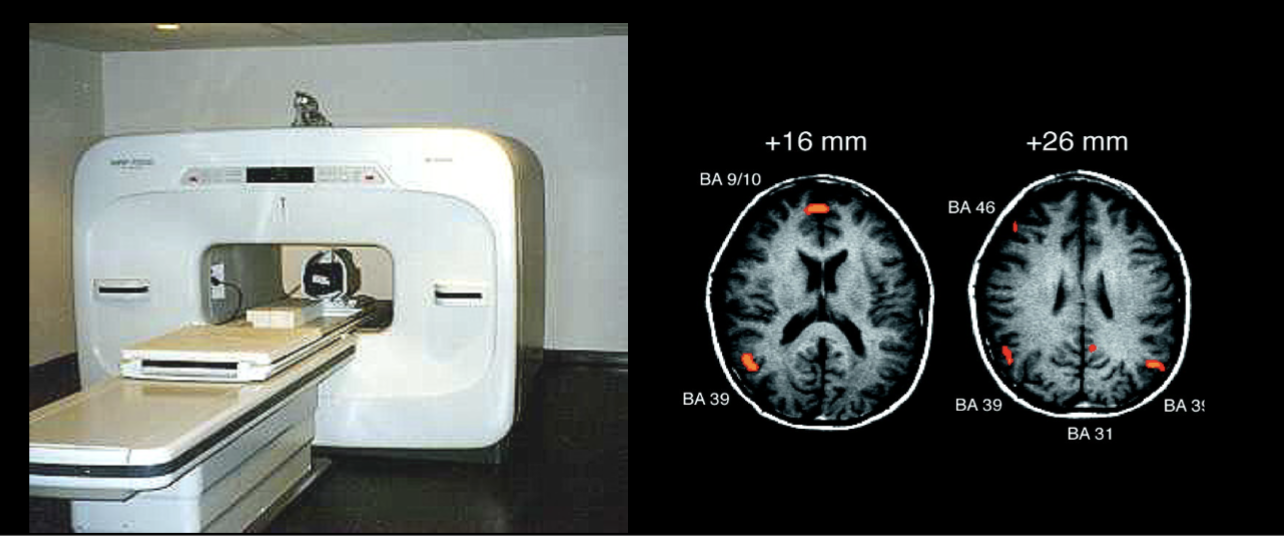

Functional magnetic resonance imagine (fMRI)

Magnetic detectors amount of hemoglobin and oxygen in different areas of the brain

Highly active areas of the brain appear to use more oxygen

Indicate where blood flows in brain for specific cognitive processing, based on magnetism

Used to develop brain regions maps

fMRI pros and cons

Provides images of the structure and activity of the brain

High detail and safe

Time-consuming, expensive, patient must be lying still on the table

Studying the relative activity of brain tissues in real-time